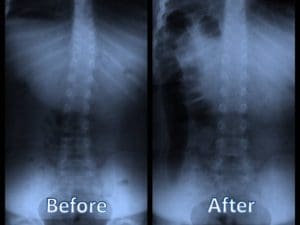

Improvement In Cobb Angle

Cobb angle is a term used to describe the degree of spinal deformities a patient experiences. It is broadly used to describe spinal damage due to injury or disease, but it is also commonly used to describe the curvature of a scoliosis patient’s spine. This measurement is used to track progression of the condition and determine what therapies or treatments are required.

In a study published in September 2011, 28 patients were evaluated and monitored in two clinics in Michigan. All patients, ranging from age 18 to 54, had been diagnosed with scoliosis. The study involved exposing the subjects to regular, consistent multimodal chiropractic rehabilitation treatment over a period of time. Once their treatment cycle was complete, the patients were monitored or a period of 24 months.

At the conclusion of the study, the patients reported improvement in pain and mobility. Additionally, the Cobb angle of each patient as well as the level of disability improved during the treatments and at the conclusion of the treatment cycle. What was most remarkable, though, was that in the subsequent follow ups, even at the end of the study 24 months later, the patients were still reporting these improvements.